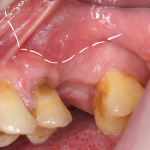

Если в зоне операции присутствует зуб, то разрез проводится по зубодесневой борозде (рис 18, 19):

Рисунок 18, 19. Схема разреза при наличии зуба в области операции

как и при проведении операции синуслифтинга одномоментно с удалением зуба (рис 20):